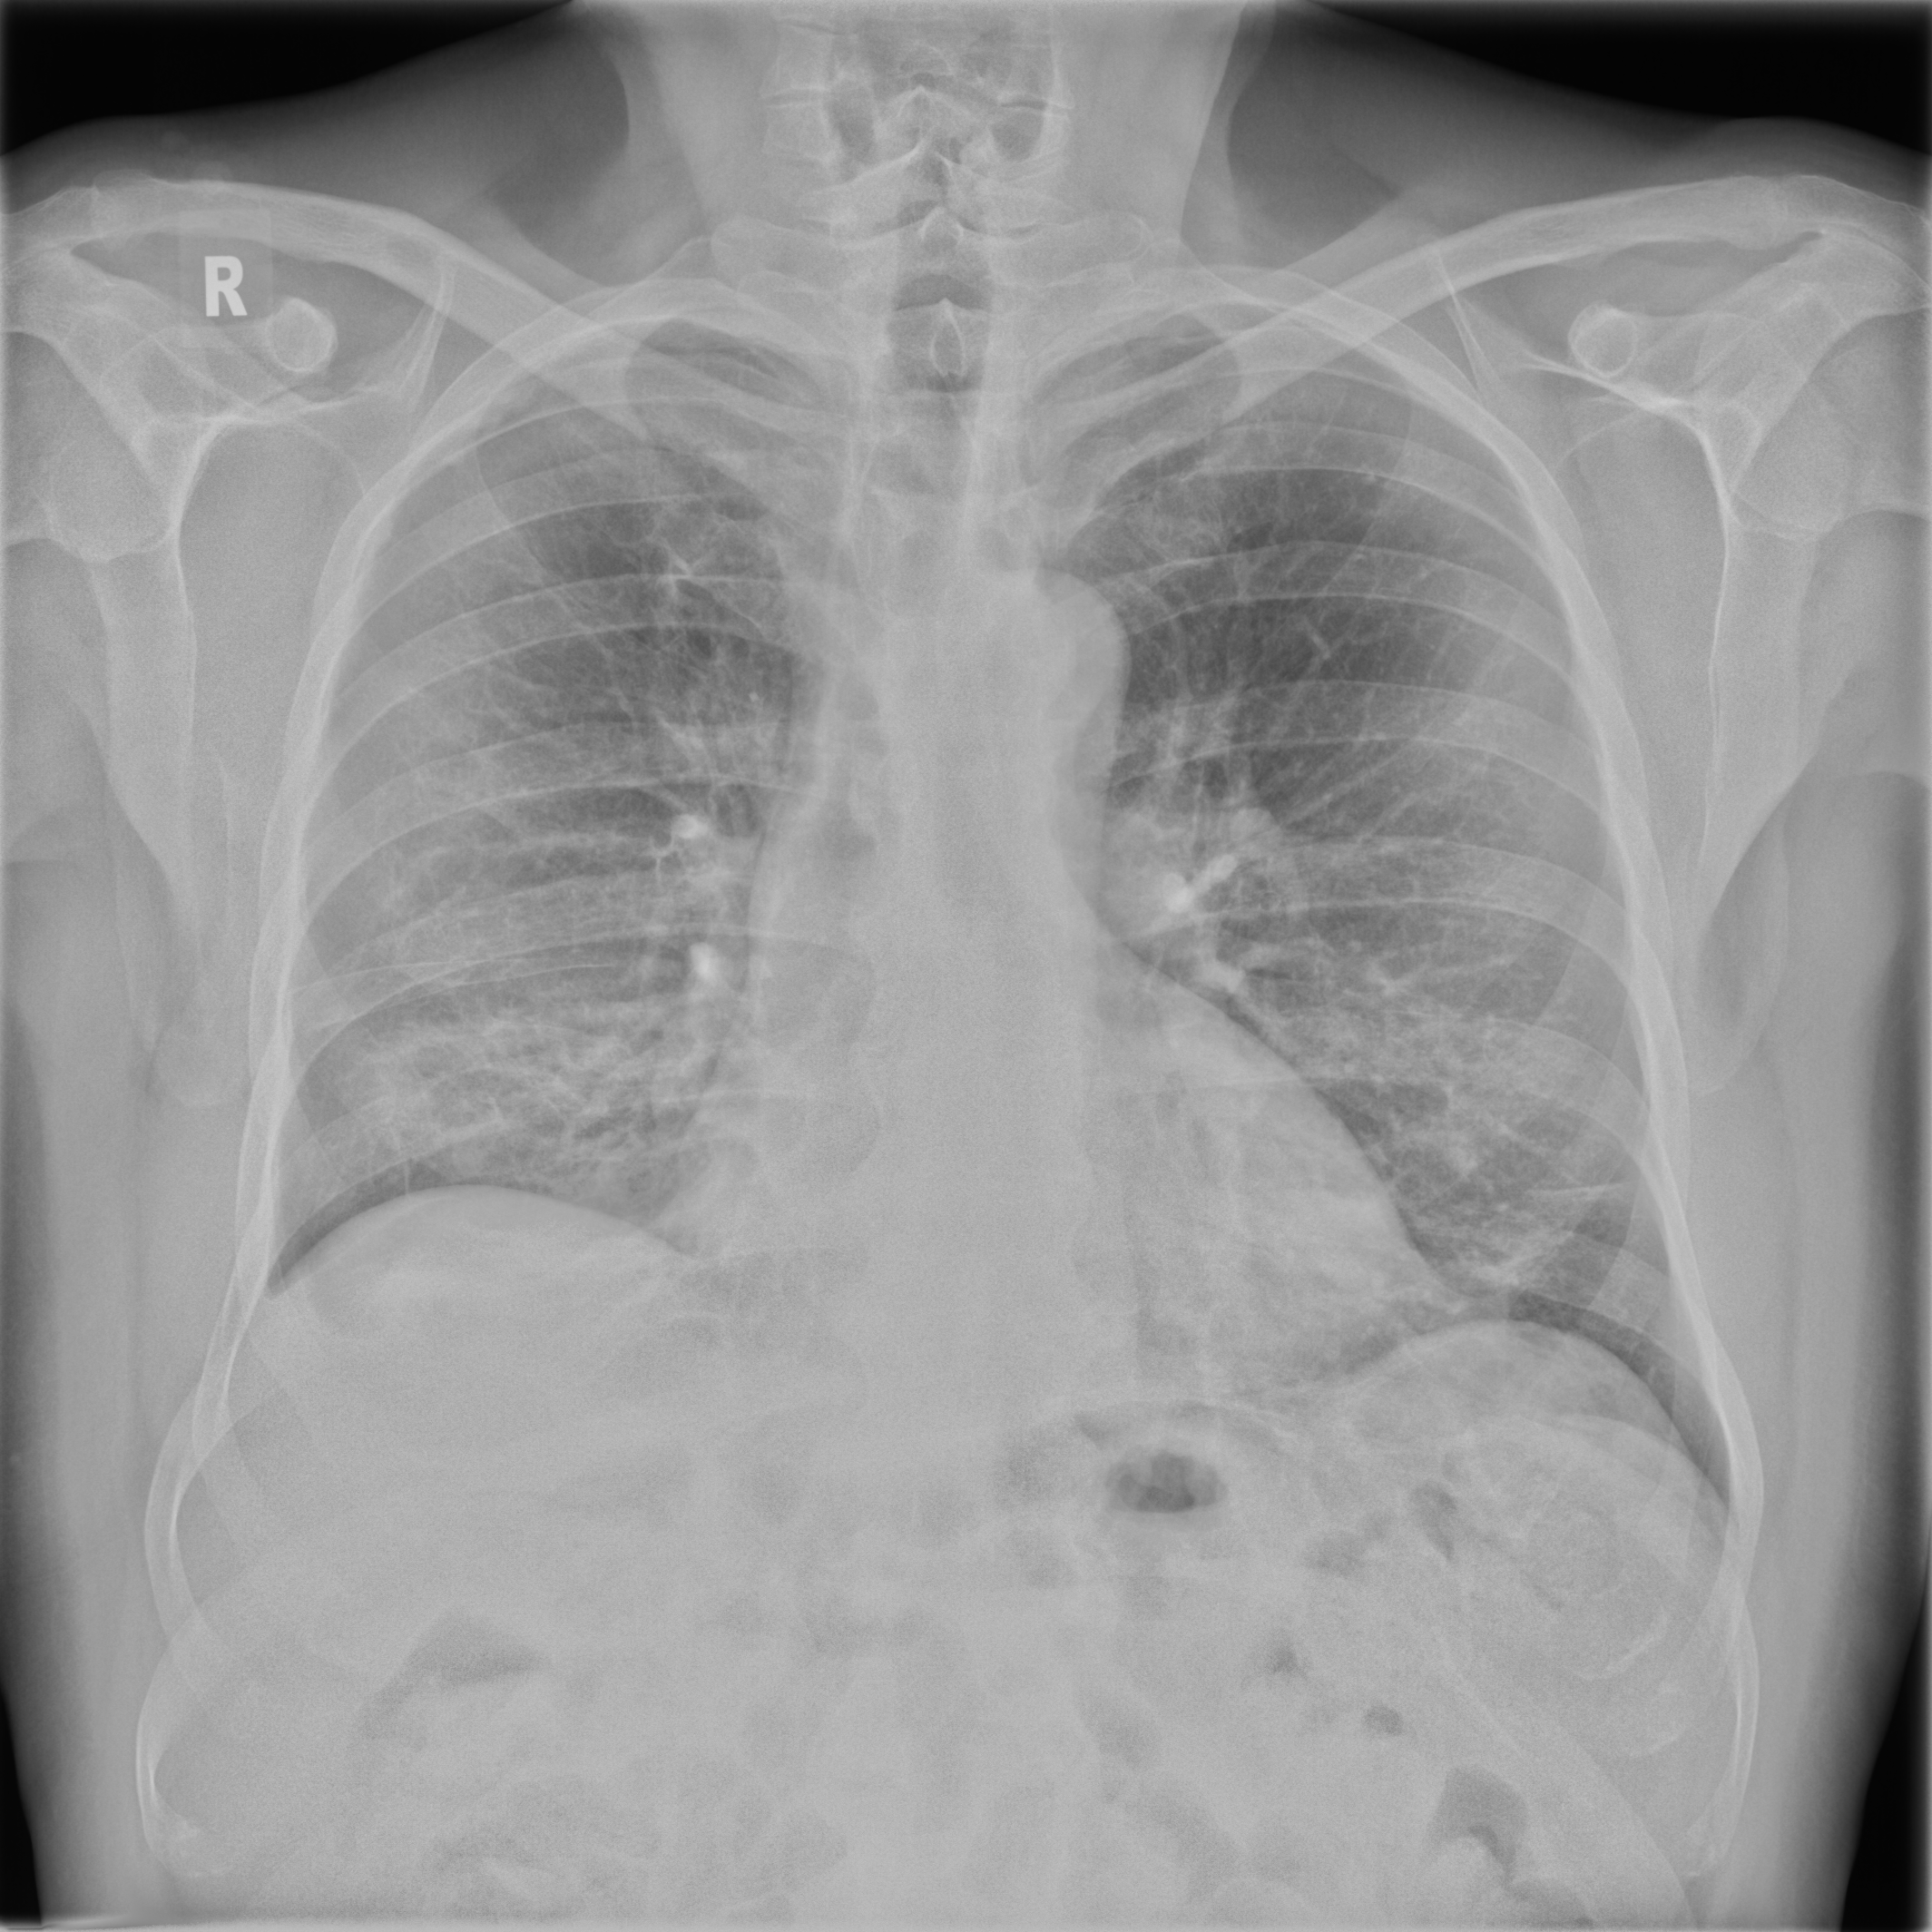

Posteroanterior chest radiographs were acquired on two imaging systems (both Discovery XR656 HD models, GE Healthcare, USA) at Cambridge University Hospitals NHS Trust. Each scanner was being set up in the hospital with different post-processing parameters (chosen by the operating radiologists), which are used here as reference images, see Figure 7 and 8(a). Additional images, serving as real-life examples of lower quality, were produced for each radiographic exposure using multiple different post-processing settings. The post-processing was applied in the hospital directly on the scanner itself by adjusting parameters in the provided framework.

Refer to caption

(a) Reference

(b) (21.1, 0.90, 0.11)

(c) (19.5, 0.88, 0.16)

Figure 7: Chest X-Ray scans with different kinds of post-processing; (a) serves as reference and (b) is wrongly judged as better visualization by PSNR/SSIM/LPIPS.

In Figure 7, contrast deviation and edge enhancement were reduced in (b), but increased in (c), the noise reduction algorithm was removed in both. The brightness was increased in both images but more so in (c) and low-contrast enhancement was removed in (b). The result is that (b) has relatively low contrast in the lungs compared to the reference (a) and radiograph (c). In Figure 8, edge enhancement has been dramatically increased in (b), whilst the contrast deviation and tissue contrast have been reduced. In (c), the brightness, tissue contrast and edge enhancement have been slightly increased. Consequently, (b) provides low contrast in the lungs with excessively prominent lung markings and vasculature which make it harder to detect abnormalities such as a pneumonia.

FR-IQA mismatches

In Figure 7 and 8 we apply the standard FR-IQA metrics to the images with diverging quality. Although it is visually obvious that image (b) has lower visual quality, it is judged wrongly as the better image by all measures in the first example Figure 7, and the results in (b) and (c) of the second example Figure 8 are quite close, where PSNR and SSIM are also providing the wrong order. This indicates that the tested standard FR metrics are not suitable to evaluate the quality of data sets with X-Ray images that have large variations regarding contrast, luminance and sharpness.